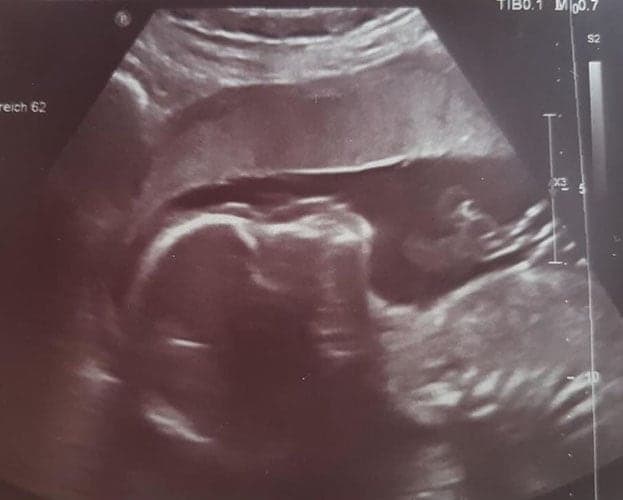

Ultraschallbilder aus dem 2. Trimester (13. bis 28. SSW)

Im 2. Trimester bekommt man oft die schönsten „Ganz-Körper“ Ultraschallbilder. Das Baby ist nun so groß, dass man alles gut erkennen kann und noch nicht zu groß, so dass es noch ganz auf das Bild passt. In dieser Zeit lässt sich meist das Geschlecht bestimmen, wobei manche Babys es einfach nicht preis geben wollen und sich immer so drehen, dass man nichts erkennen kann.